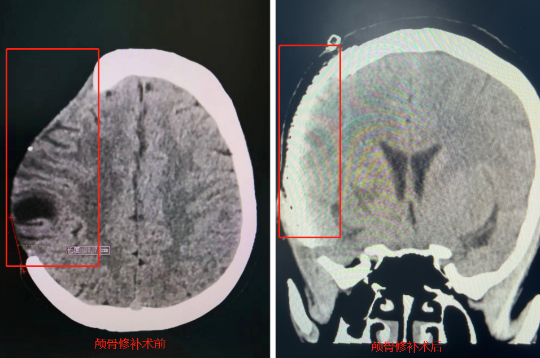

在经过一段时间治疗后,高女士顺利出院并开始规律地服用抗HIV药物。术后一年多,她的病毒载量得到有效控制。唐忠团队为她进行了颅骨修补手术,用3D打印的钛合金材料修补了当时去骨瓣减压术形成的12厘米×10厘米骨窗。

“如果不修补颅骨,高女士会反复头晕头痛和记忆力减退,修补有利于颅脑组织的恢复。”唐忠介绍道。